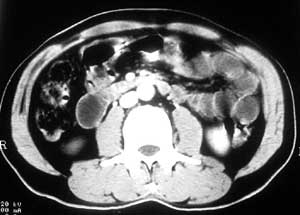

患者,男,57岁,梗阻性黄疸10余天。

这个病例胰头无明显增大,胆总管扩张明显而肝内胆管扩张更不明显,病程较短,

注意到十二指肠乳头明显突出,但尚光滑。分析以下可能性:

1、十二指肠乳头本身的病变,如乳头炎症;

2、急性乳头水肿,胆总管下端结石排石后乳头水肿;

3、壶腹部胆总管下端肿瘤累及十二指肠乳头。

十二指肠乳头粘膜慢性非特异性炎症